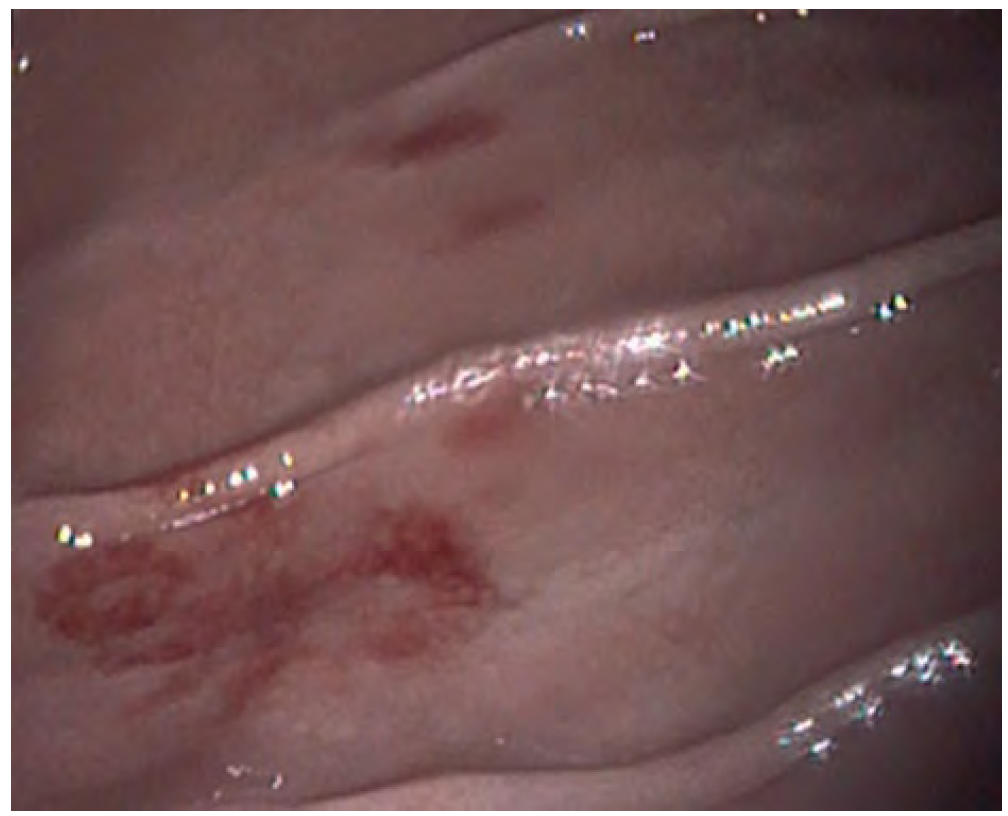

- 一些患者可能会出现呕血、黑便(图1)和/或并发腹泻。

图1. 一只患有近端胃肠道(胃部)出血的狗出现黑便(柏油样粪便)。